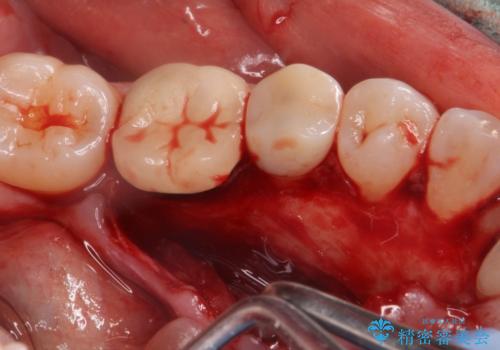

骨隆起除去

- 骨隆起が舌にあたり不快感があるので骨隆起をとりたくて来院。

静脈内鎮静麻酔下で骨隆起を除去を行いました。

骨隆起がなくなり不快感がなくなり大変満足して頂けました。